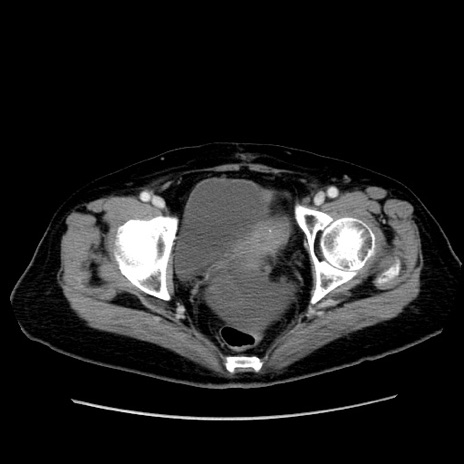

症例19(横断像)

【症例】80歳代女性

【主訴】下腹部痛

【現病歴】約8時間前より下腹部痛の出現あり、救急外来受診。

【既往歴】両側付属器切除

【身体所見】意識清明、下腹部正中に手術痕あり、その部位に一致して圧痛と反跳痛あり。腸蠕動音は亢進。

【データ】WBC 9300、CRP 0.15